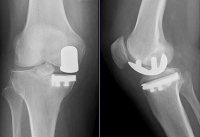

Yup. A partial left knee replacement – the medial compartment (the inner aspect of the knee). It’s been pending for a long time – had meniscus surgery in 2004 and been taking the hyaluronic acid shots for the last two and a half years. And it helped greatly – for awhile. But now time for surgery.

And the bone on bone osteoarthritis had nothing to do with 20 years of playing rugby; everything to do with being bowlegged! Hahaha!